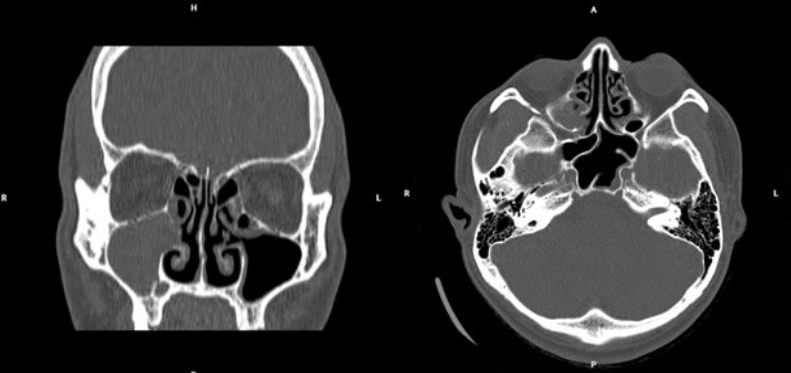

| Hình ảnh chụp cắt lớp vi tính xoang phát hiện tình trạng viêm đa xoang mức độ III. |

Kết quả chụp cắt lớp vi tính xoang xác định tình trạng viêm đa xoang mức độ III theo phân độ Lund-Mackay. Đặc biệt, nuôi cấy vi khuẩn cho thấy tác nhân gây bệnh là Haemophilus influenzae, một trong những nguyên nhân phổ biến gây viêm xoang cấp mủ.